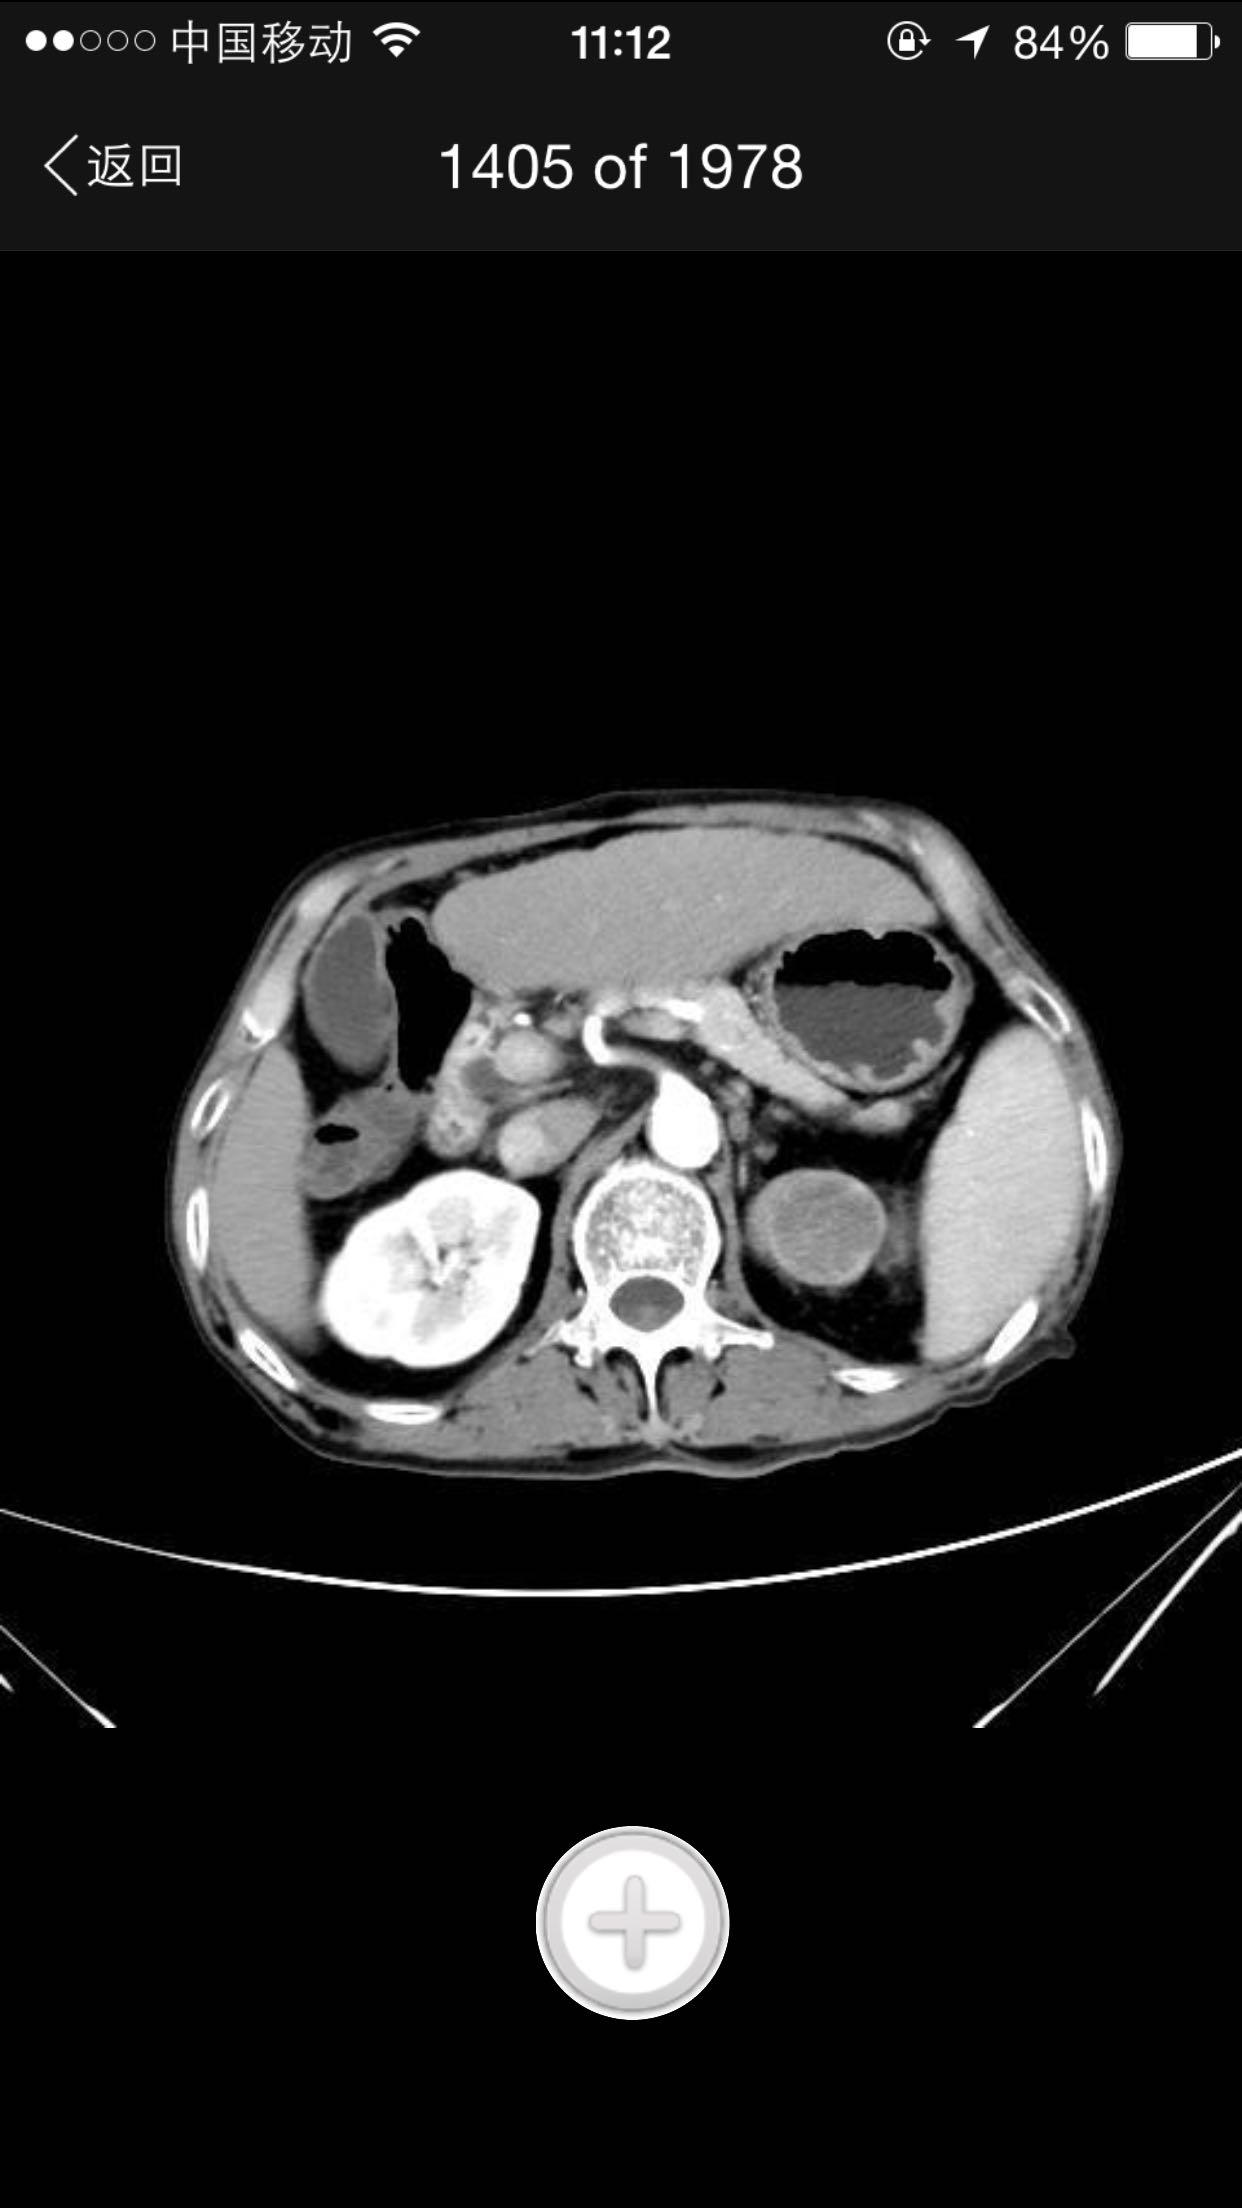

排尿困难,尿潴留入院。诊为前列腺增生症,拟行手术治疗。完善术前检查,泌尿系CT检查发现左肾占位,左肾结石并左肾重度积水,左肾萎缩等。既往患者肺结核病史,服药控制半年余。

查体:腹平软,无压痛及反跳痛,无肾区叩痛,肛诊前列腺明显增大,中央沟消失,无硬结,无压痛。术前强化CT提示左肾癌。

术前诊断:1、左肾癌2、左肾结石3、左肾积水4、左肾萎缩5、前列腺增生6、肺结核 入院后完善检查,拟行TURP,因发现左肾癌,改为先行肾手术。患者左肾癌,同时左肾结石,肾萎缩,决定行根治性肾切除,拟腹腔镜下手术,患者家属不同意,改开放手术,全麻下行根治性左肾切除。术后剖开标本如下图,肿瘤位于肾上极,中间黑色为结石。